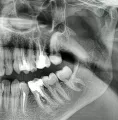

Первые дни только привыкал к шинам, но быстро адаптировался, так как не впервой. От госпитализации я отказался, решил, что в домашних условиях справлюсь. Сделал контрольный снимок, проконсультировался с хирургом-стоматологом и он, посмотрев на снимок и на шины, сказал, что процесс заживления идёт нормально.

Снимок прилагаю (был сделан на 5-й день после шинирования).

Теоретически все нормально, но справа имеется серьёзный костный дефект с повреждением нижнечелюстного канала. Рекомендую Вам обратиться к лечащему врачу.